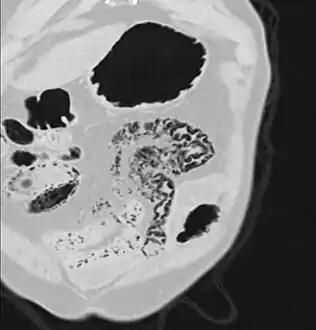

Pneumatosis intestinalis at computed tomography in intestinal ischemia. Lung window for better representation of the gas deposits in the intestinal walls. Coronal reconstruction.